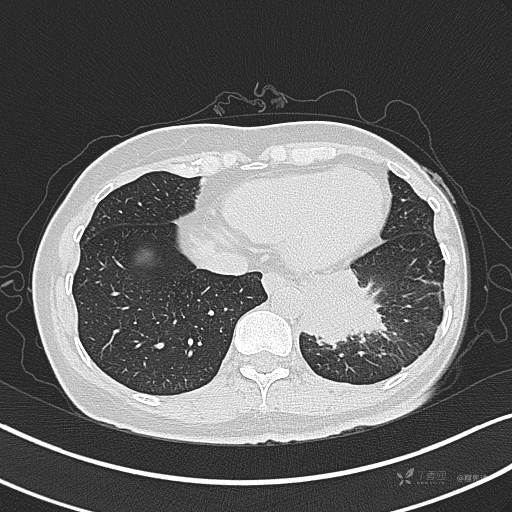

增强动脉期

动脉期CT值约74HU